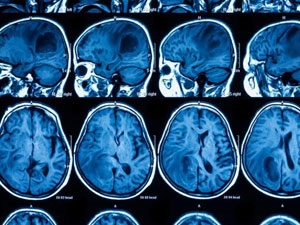

மருத்துவ உலகின் புதிய புரட்சி: தோலின் உயிரணுக்கள் மூலம் மூளைப்புற்று நோயை குணப்படுத்தும் முறை கண்டுபிடிப்பு

மனிதத் தோலில் உள்ள உயிரணுக்களை (செல்களை) குருத்தணுக்களாக மாற்றி மனிதர்களின் மூளையில் உருவாகும் கிலியோபிளாஸ்டோமா என்ற புற்றுக்கட்டியை குணப்படுத்தும் நவீனவகை மருத்துவத்தை அமெரிக்க மருத்துவ ஆய்வாளர்கள் கண்டுபிடித்துள்ளனர்.கிலியோபிளாஸ்டோமா என்ற மூளைப் புற்றுக்கட்டிக்கு சிகிச்சை அளிப்பது மிகவும் சிக்கலானதாக கருதப்படுகிறது. இந்த சிகிச்சையில் உயிர்பிழைக்கும் வாய்ப்பு 30 சதவீதம் மட்டுமே உண்டு. மீதி நோயாளிகள் சிகிச்சை தொடங்கிய இரண்டு ஆண்டுகள்கூட உயிர் வாழ்வது கடினம் என்ற நிலைதான் நீடித்து வருகிறது.

புற்றுக்கட்டியை ஆபரேஷன் மூலம் நீக்கிவிட்டாலும் புற்றின் பாதிப்பு மூளையின் ஆழ்ந்த பகுதிவரை ஊடுருவி விடுவதால் ஆபரேஷனுக்குப் பிறகு அங்கிருந்து வெளியாகும் தாக்கம் மீண்டும் புதிய கட்டியாக உருவாகி விடும்.

இந்த குருத்தணுக்கள் ஒருவித புரதத்தை வெளிப்படுத்தியவாறு மூளையின் வெளிப்புறம் மட்டுமின்றி ஆழ்ந்த பகுதிகளுக்கும் சென்று செயலாற்றுவதால் கிலியோபிளாஸ்டோமா-வை முழுமையாக கொல்வதுடன் மீண்டும் புற்று ஏற்படாதவாறு பாதுகாக்கின்றன என்பது இந்த ஆய்வில் கண்டறியப்பட்டுள்ளது.